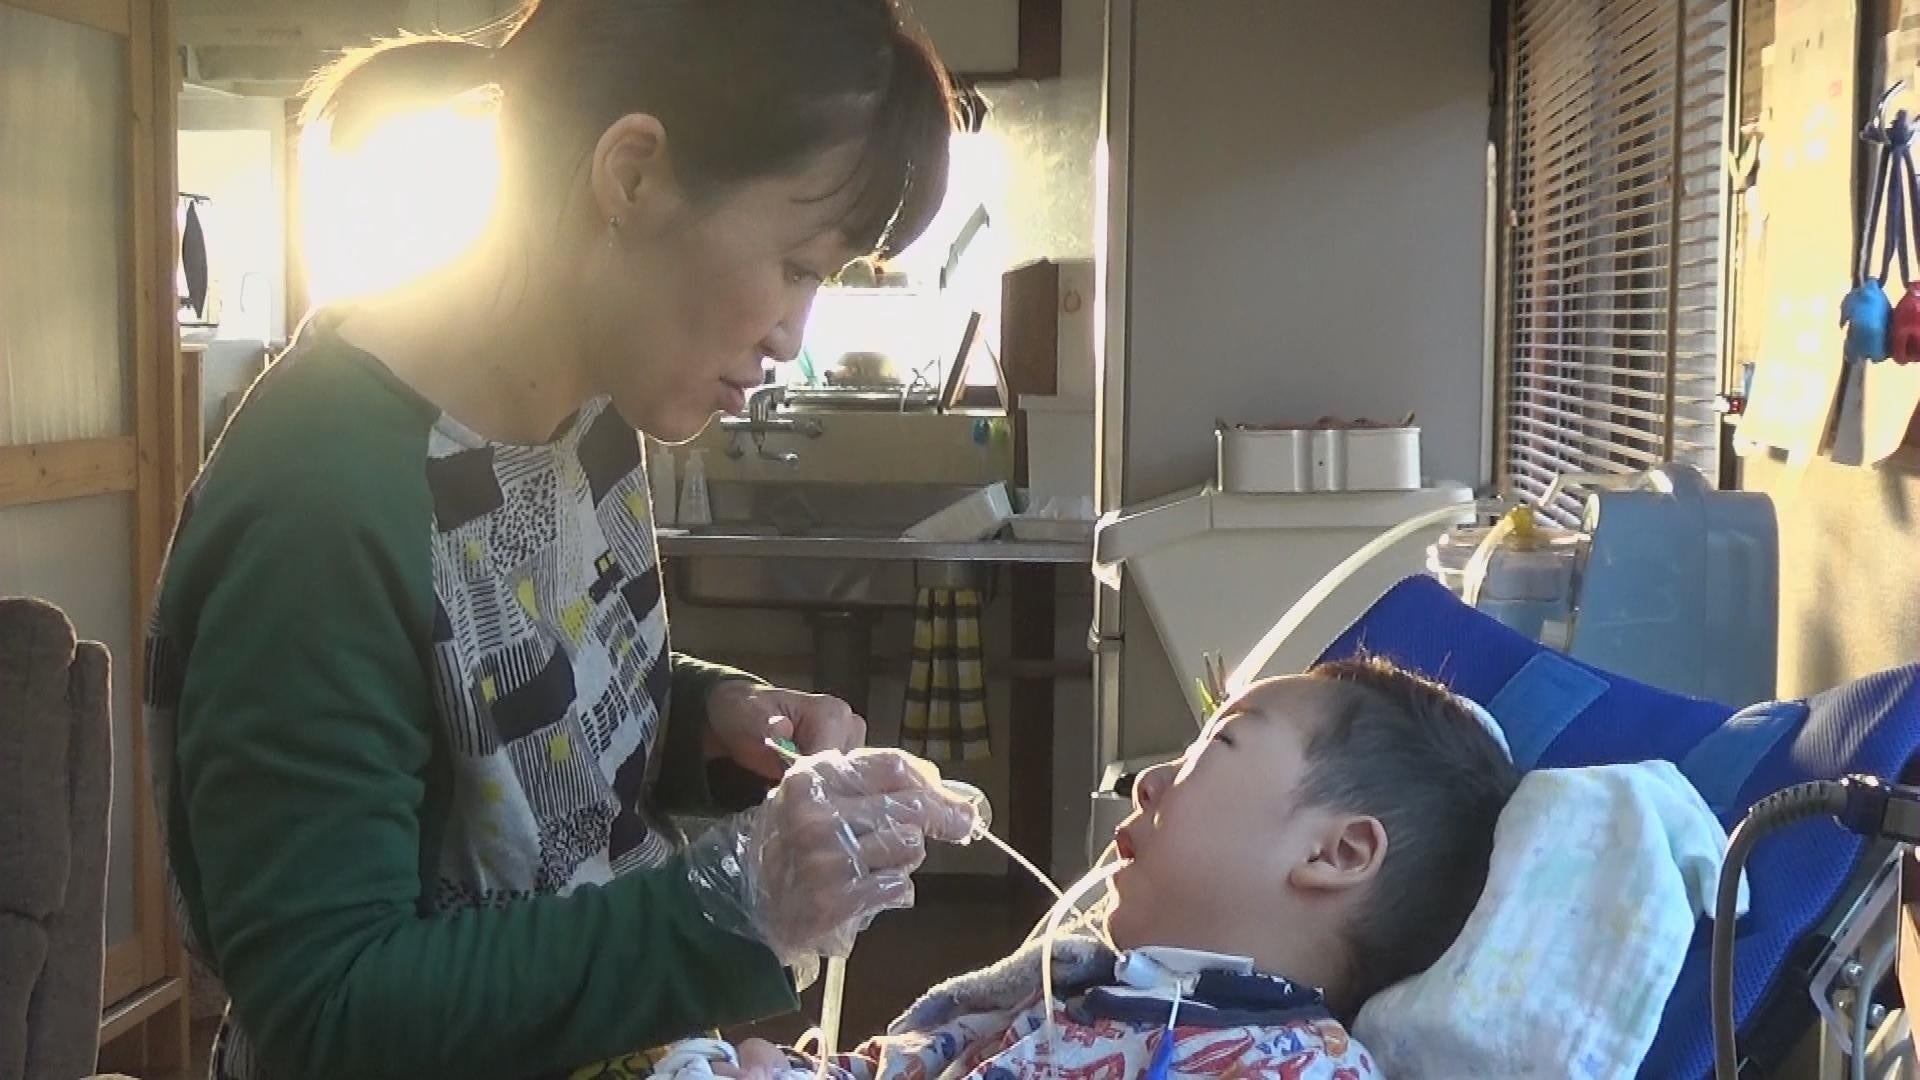

目撃者f 消えないアラーム~医療的ケア児 命つないだ先に~

深夜3時、異常を知らせるアラームの音に起こされる桝田夫婦。わが子の呼吸器が外れた音です。桝田夫婦の長男・きったくん(6)は常にたんの吸引や経管栄養が必要な「医療的ケア児」です。一方、これまでの障害児支援制度の枠組みに当てはまらないのが「動ける医療的ケア児」です。久留米市の平尾悠輝くん(6)の願いは友達と同じ学校で学ぶこと。しかし、そこには安全を巡って大な壁が立ちはだかります。医療の進歩によって増え続ける医療的ケア児。救われた命のその先に一体何が待ち受けているのでしょうか。

目撃者f 消えないアラーム~医療的ケア児 命つないだ先に~ ©株式会社福岡放送

目撃者f 消えないアラーム~医療的ケア児 命つないだ先に~ ©株式会社福岡放送